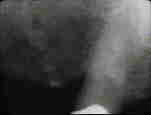

La radiografía del diente revela un defecto

intraóseo en mesial que parece también extenderse a palatino. |